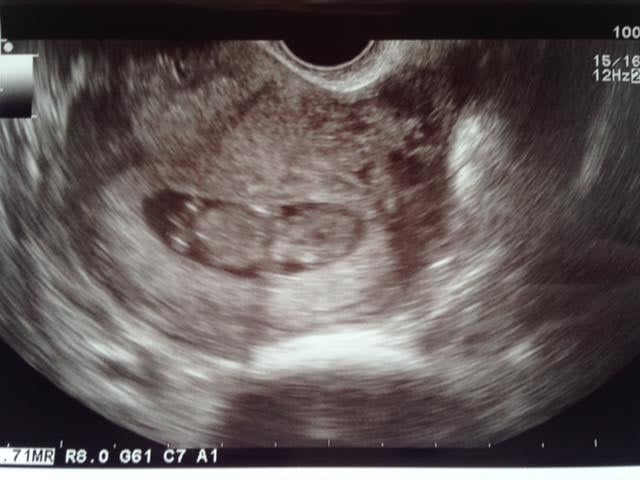

From my ultrasound today, at 8 weeks 6 days. Heart rate was 176 BPM. All the nausea finally feels worth it! It was such a relief to see a healthy bean in there. Personally, I think it slightly resembles Stimpy.